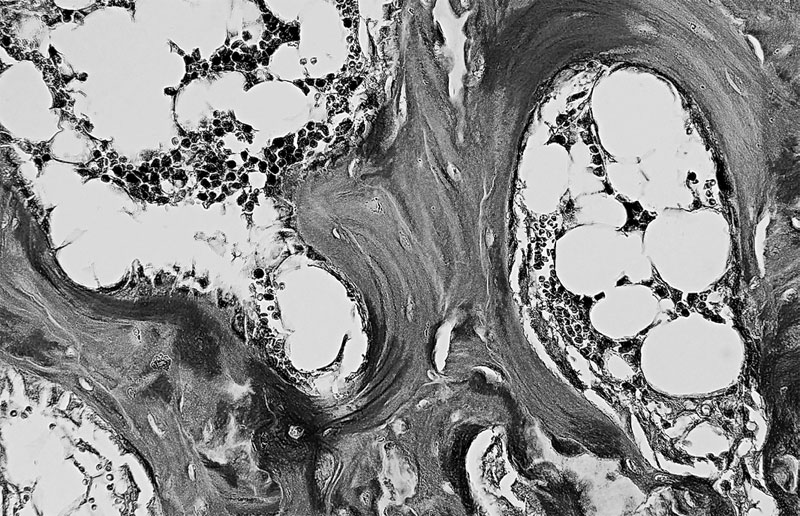

Особенность третья — костная ткань имеет пластинчатое строение. Каждая пластинка представляет собой тонкий пучок параллельно расположенных коллагеновых волокон, между которыми находятся остеоциты и аморфное вещество, содержащее кристаллы минеральных солей. Волокна соседних пластинок располагаются под углом друг к другу, часть их переходит из одной пластинки в другую, что обуславливает их плотное соединение, а, следовательно, и высокую прочность костей. Пластинок, располагаются вокруг каналов, в которых проходят кровеносные сосуды и нервы, образуя многослойные концентрические цилиндры.

Костные пластинки, образующие канал для кровеносного сосуда (в центре)